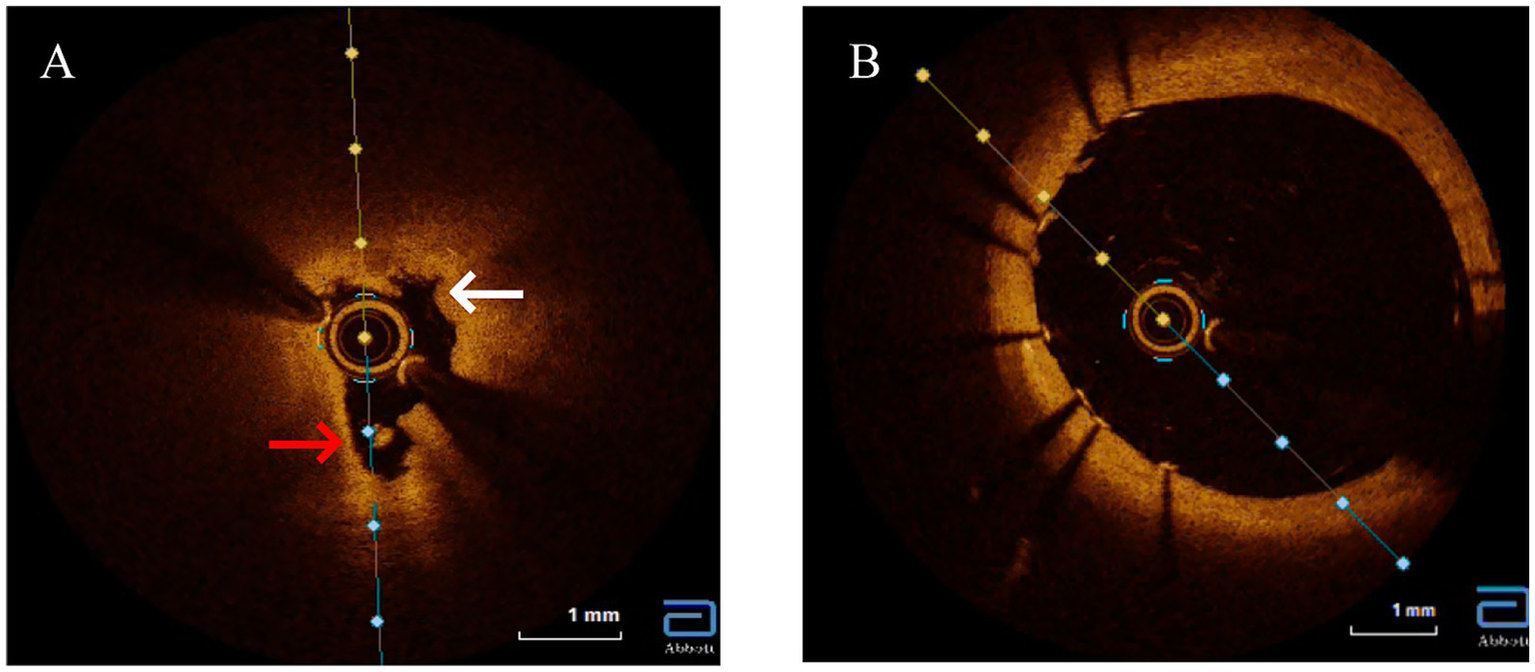

Figure 4

Optical coherence tomography (OCT) imaging of the left main ostium. (A) Baseline OCT reveals features pathognomonic for syphilitic vasculitis, including severe luminal narrowing, marked disruption of the medial layer (white arrows), obliterated vasa vasorum appearing as signal-poor voids, and diffuse adventitial microcalcifications (red arrows). Crucially, key features of atherosclerosis, such as a lipid core or a distinct fibrous cap, are absent. (B) Post-intervention, showing a well-apposed stent and restoration of the vessel lumen.

Given the constellation of ostial-predominant coronary disease, aortic aneurysm, and the profound discordance between angiographic severity and the objective lack of atherosclerosis (CACS = 0, normal CIMT, absence of traditional risk factors), an alternative etiology such as aortitis was strongly suspected. The positive TPPA test, indicating past or current Treponema pallidum infection, made cardiovascular syphilis the leading diagnostic consideration. To confirm or exclude this suspicion and to guide the optimal intervention, intravascular OCT was performed. Recognizing OCT’s unique capability to evaluate plaque morphology, composition, and stenosis etiology while assessing PCI risks, we opted for OCT-guided PCI rather than coronary artery bypass grafting (CABG) due to the focal ostial involvement and Rentrop grade 2 collateral circulation. OCT revealed severe ostial stenosis with medial layer disintegration, hyporeflective adventitial microcalcifications, and vasa vasorum obliteration (Figure 4A). Figure 4B showed stent implantation after PCI treatment. These features distinguished syphilitic vasculitis from atherosclerosis (which typically shows lipid-rich plaques) or Takayasu arteritis (diffuse intimal thickening).

Cardiovascular syphilis represents a late-stage complication of Treponema pallidum infection that continues to pose significant diagnostic challenges in contemporary practice (4). Typically manifesting 10–30 years after initial exposure, this condition predominantly affects the aorta, coronary ostia, and valvular structures, with classic presentations including aortitis, aortic regurgitation, and aneurysmal dilation (5). Our case illustrates a classic diagnostic dilemma of cardiovascular syphilis: proximal coronary stenosis. This dilemma was further compounded by serological ambiguity—a non-reactive RPR despite a positive TPPA—a pattern characteristic of late-stage disease due to immunological exhaustion (6). Given this ambiguity, our first critical step was to rule out alternative diagnoses, particularly atherosclerosis. In such clinically ambiguous scenarios, OCT emerges as a crucial diagnostic tool, providing detailed microstructural characterization when histopathological confirmation is unavailable (7). The OCT findings in our patient, including medial layer disruption, hyporeflective adventitial microcalcifications, and vasa vasorum obliteration, created a distinctive morphological signature differentiating syphilitic involvement from atherosclerotic disease or idiopathic aortitis. These features contrast sharply with the lipid-rich plaques with fibrous caps characteristic of atherosclerosis or the concentric laminar inflammation seen in giant cell arteritis, instead demonstrating fragmented elastic laminae and peri-adventitial scarring consistent with chronic ischemic injury from endarteritis obliterans (8). The absence of lipid pools or thrombus on OCT argued against acute plaque rupture, while the ostio-proximal localization with Rentrop grade 2 collateralization supported a slowly progressive inflammatory stenosis process (9). This case unequivocally underscores the limitation of relying solely on RPR in late-stage syphilis. A non-reactive RPR does not exclude active vasculitis, as evidenced by the positive TPPA and, crucially, the definitive OCT findings. This discrepancy, potentially reflecting the prozone phenomenon or a serofast state, underscores the necessity of a high clinical suspicion and the use of adjunctive imaging in such cases.

The diagnostic value of OCT extends to its ability to differentiate syphilitic vascular involvement from other vasculitides (10). While Takayasu arteritis typically presents with diffuse intimal thickening and homogeneous signal intensity, syphilitic lesions demonstrate irregular medial hyporeflectivity. Similarly, IgG4-related aortitis primarily shows adventitial fibrosis without the microcalcifications characteristic of syphilis, and atherosclerotic lesions exhibit features like thin-cap fibroatheromas and necrotic cores that are absent in syphilitic vasculopathy (11). Based on these observations, we propose three OCT hallmarks of cardiovascular syphilis: focal medial disintegration, adventitial microcalcifications, and obliterated vasa vasorum—though these findings require validation in larger patient cohorts. The OCT findings were pivotal, as they provided the definitive morphological evidence that confirmed our suspicion after we had systematically excluded atherosclerosis. Indeed, the most critical step in our diagnostic process was this systematic exclusion. Several key pieces of evidence converged to make atherosclerosis an unlikely cause for the patient’s complete left main ostial occlusion. First, the patient lacked major traditional risk factors, including smoking, hypertension, and diabetes. Second, and most powerfully, the coronary artery calcium score (CACS) was zero. CACS is a highly sensitive marker for the presence of coronary atherosclerosis, and a score of zero confers an extremely low probability of obstructive atherosclerotic disease. The severe, non-calcified ostial lesion in our patient is therefore highly atypical for an atherosclerotic origin. Third, the absence of atherosclerosis was a systemic finding, supported by a normal carotid intima-media thickness and the lack of plaques in other major arteries. Finally, the lesion’s location—perfectly confined to the coronary ostium, adjacent to a dilated aortic root—is a classic hallmark of syphilitic aortitis, which primarily affects the aortic media and adventitia, leading to secondary ostial narrowing. In contrast, atherosclerotic lesions are typically more diffuse and located distal to the ostium within the coronary artery itself (Table 1).